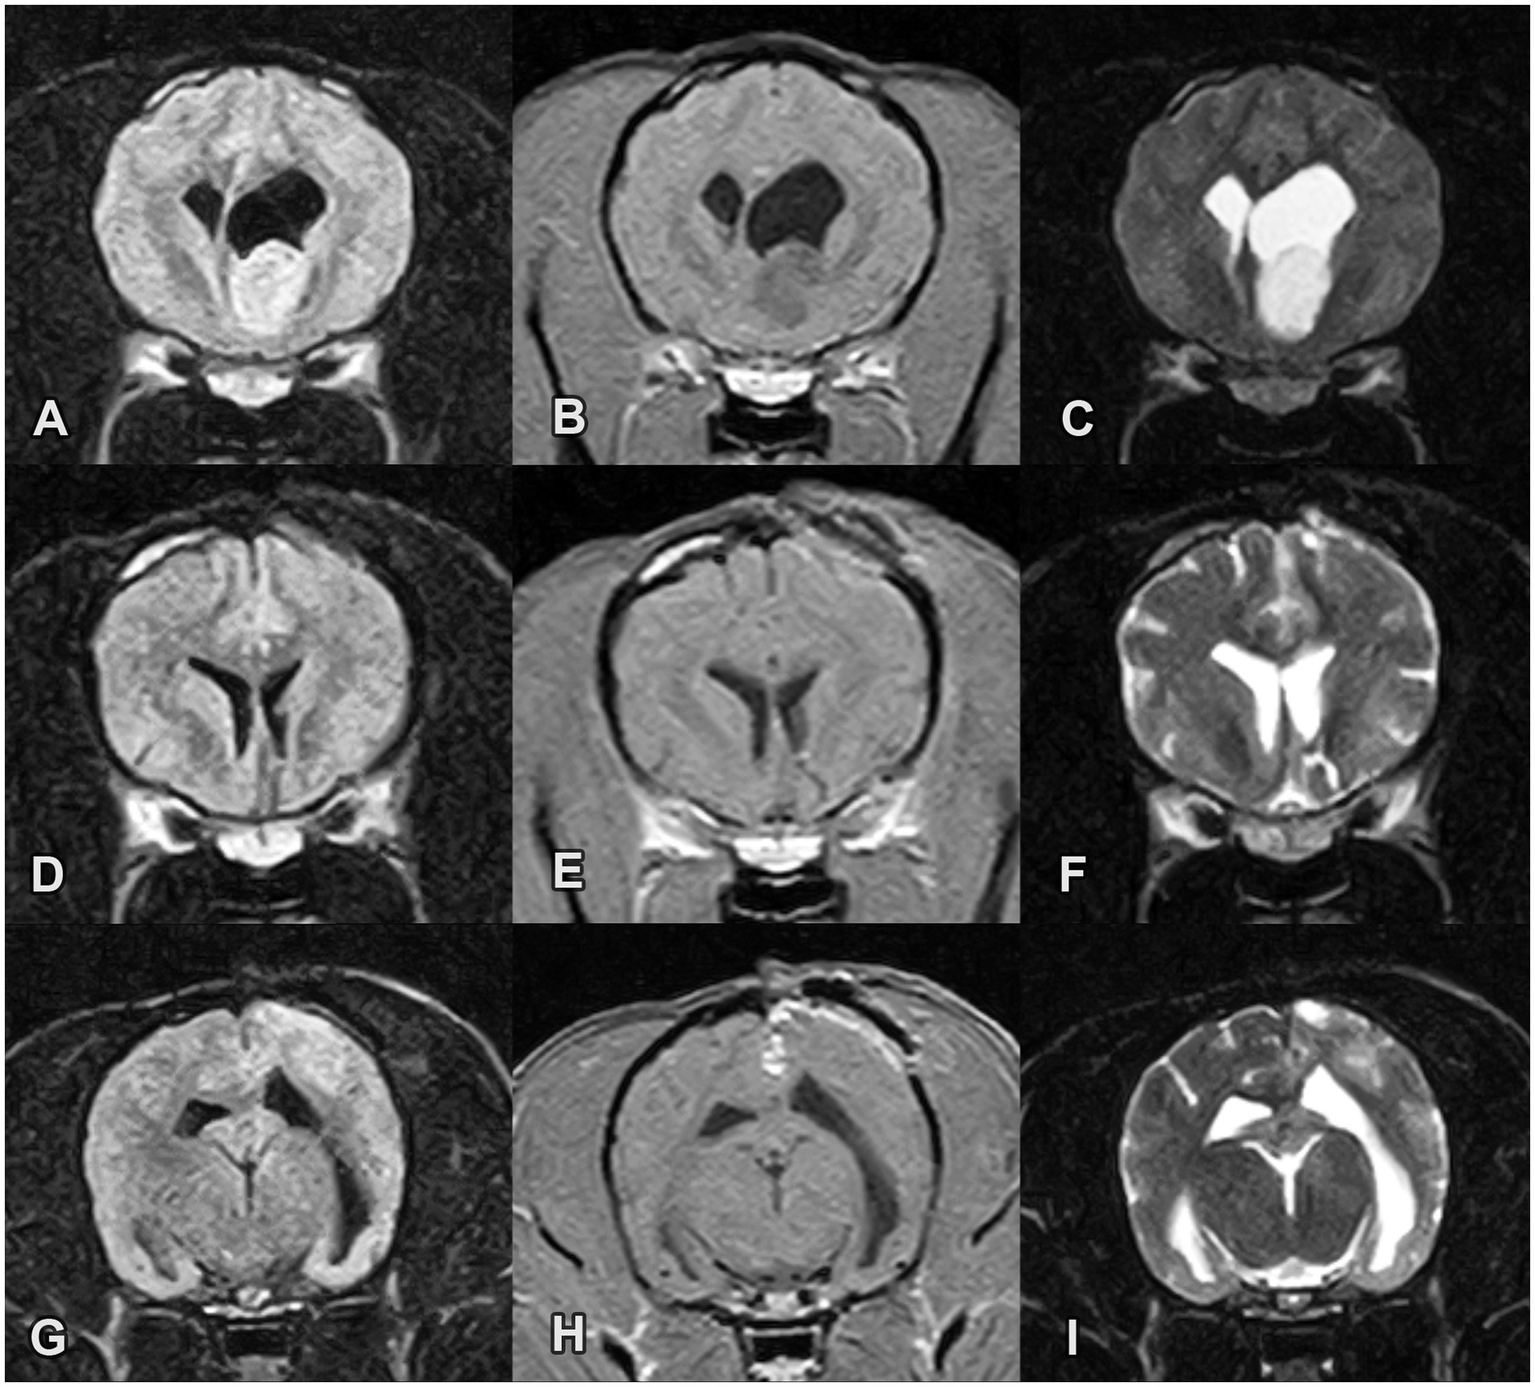

Figure 3

Pre- and post-operative MRI images of an intraventricular astrocytoma in the rostral horn of the left lateral ventricle in Case 3. (A-C) Pre-operative transverse images (A) FLAIR, (B) T1W post-contrast and (C) T2W images reveal a FLAIR/T2W hyperintense and T1W hypointense mass without contrast enhancement. (D–F) Post-operative transverse images at the site of the previous mass. The mass is no longer present. (G-I) 2-month post-operative transverse images (G) FLAIR, (H) T1W post-contrast and (I) T2W image. Multifocal T2 hyperintensities in the subcortical white matter and contrast enhancement in the region of the surgical approach are noted. The lateral ventricles are still mildly enlarged but their size decreased in comparison with the preoperative status.

Levetiracetam and prednisolone treatments were continued at the preoperative doses. Prednisolone was tapered and discontinued 1 month after the surgery. Two months after surgery, 2 GTCS occurred which were treated with a diazepam rectal solution (1 mg/kg) at home. The levetiracetam dose was increased to 30 mg/kg TID, PO, and gabapentin (10 mg/kg BID, PO) was used as an add-on ASM. MRI was repeated 2 months after surgery. The lateral ventricles were still mildly enlarged, but their size decreased compared with the preoperative status. No intraventricular mass was observed. Multifocal T2 hyperintensities in the white matter and contrast enhancement were noted in the region of the surgical approach (Figures 3D–I).